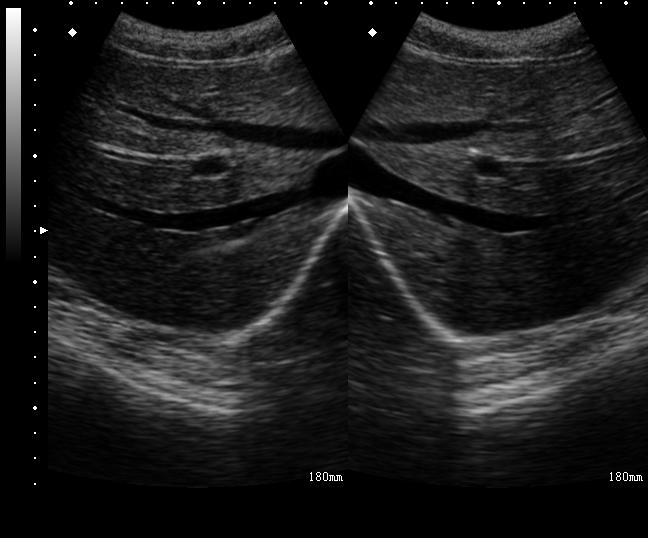

选用7~13MHz的线阵探头。使用短轴平面内技术。将探头和肋骨垂直放置,即可显示肋间神经的横截面超声图。肋骨呈城垛样表现,表面高回声,深部低回声。肋骨之间由高回声胸胸膜相连。肋骨下双腿和胸膜的成角处即为肋间神经的位置。肋间血管细小或被肋骨阻挡,一般很难在超声上显示。

临床上可从后路(肋骨角处)、侧路(腋后线附近)、前侧路(腋前线附近)进行肋间神经阻滞。在行胸7以上水平后路肋间神经阻滞时,患者两臂向前并略内旋,使两侧肩胛骨向外。常用短轴平面内技术。将探头和肋骨垂直放置,即可显示肋间神经的横截面超声图。从探头的下方进针,看到针尖到达肋骨下缘和胸膜的成角处即可,注射3~5ml局部麻醉药。可看到相应位置胸膜下陷(图29-1,图2)。